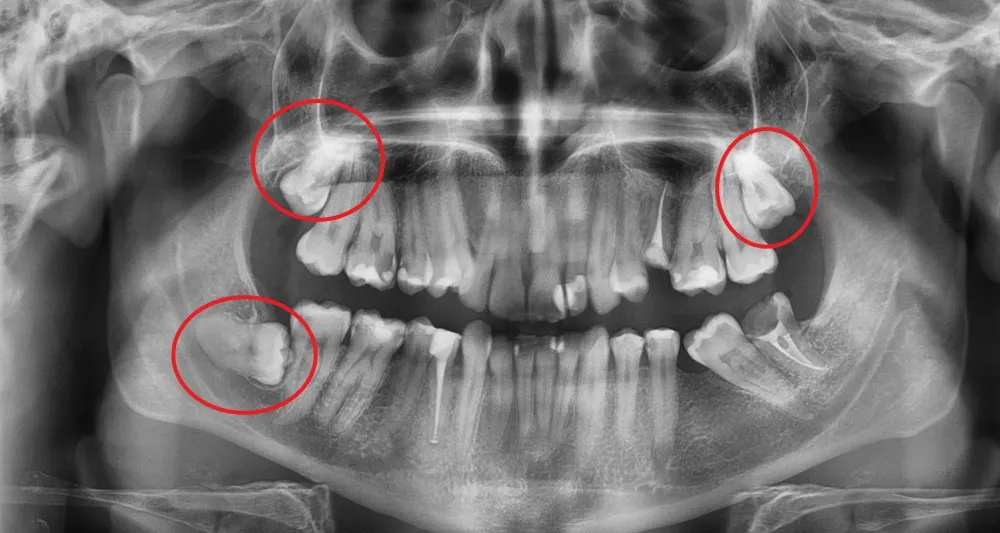

Nie każda ekstrakcja jest prosta. Skomplikowane i rozległe zabiegi, takie jak chirurgiczne dłutowanie zęba (np. zatrzymanej ósemki), wiążą się ze znacznie większym urazem tkanek i dłuższym czasem gojenia. W takich sytuacjach ryzyko powikłań infekcyjnych jest podwyższone. Dlatego też, po tego typu zabiegach, stomatolodzy znacznie częściej decydują się na przepisanie antybiotyku, aby profilaktycznie zabezpieczyć pacjenta przed rozwojem zakażenia i wspomóc proces gojenia.

Wyrwanie ósemki: dlaczego antybiotyk jest częstszym wyborem?

Specyfika usuwania zatrzymanych ósemek

Usunięcie zębów mądrości, zwłaszcza tych zatrzymanych w kości lub częściowo wyrżniętych, to zabieg o zupełnie innej specyfice niż ekstrakcja zwykłego zęba. Często wymaga on nacięcia dziąsła, usunięcia fragmentu kości i szycia rany. To wszystko sprawia, że jest to procedura o podwyższonym ryzyku powikłań zapalnych. Zatrzymane ósemki często są źródłem przewlekłych stanów zapalnych, a ich usunięcie może otworzyć drogę bakteriom do głębszych tkanek. Właśnie dlatego stomatolodzy znacznie częściej decydują się na profilaktyczne przepisanie antybiotyku po chirurgicznym usunięciu zębów mądrości, aby zminimalizować ryzyko infekcji i zapewnić spokojny proces gojenia.

Profilaktyka antybiotykowa: Zapobiegać, a nie leczyć

W przypadku skomplikowanych zabiegów, takich jak chirurgiczne usuwanie ósemek, koncepcja profilaktycznego podawania antybiotyków jest bardzo ważna. Nie chodzi o leczenie już istniejącej infekcji, ale o zapobieganie jej rozwojowi. Podanie antybiotyku przed lub krótko po zabiegu, w odpowiedniej dawce i przez określony czas, ma na celu zredukowanie liczby bakterii w polu operacyjnym i w krwiobiegu, co znacząco zmniejsza ryzyko powikłań infekcyjnych. To przemyślana strategia, która ma chronić pacjenta przed niepotrzebnym cierpieniem i dalszymi komplikacjami.